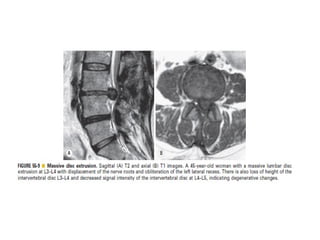

The spine is made up of vertebrae separated by intervertebral discs that allow movement and provide shock absorption. Diagnostic imaging plays an important role in evaluating the spine for conditions like fractures, disc herniations, spinal stenosis, and tumors. Imaging modalities like X-rays, CT scans, MRI, and bone scans can detect abnormalities and aid physicians in diagnosing and treating various spinal disorders.